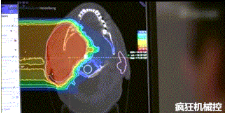

▲360°重離子治療一體機治療腫瘤

360°重離子治療一體可從任何角度用重離子(碳,氦,氧)和質子(氫)照射腫瘤。此外,基于機器人的治療臺可以通過六種方式進行調整。

光柵掃描被集成到360°重離子治療一體機中,這種極其精確的照射方法以毫米為單位掃描腫瘤,可以保護健康組織且只治療腫瘤區(qū)域。

特別是腫瘤在高度輻射敏感位置或者諸如視神經(jīng)附近的復雜位置,可以通過選擇最佳射束入射角來減小這些器官的損傷。